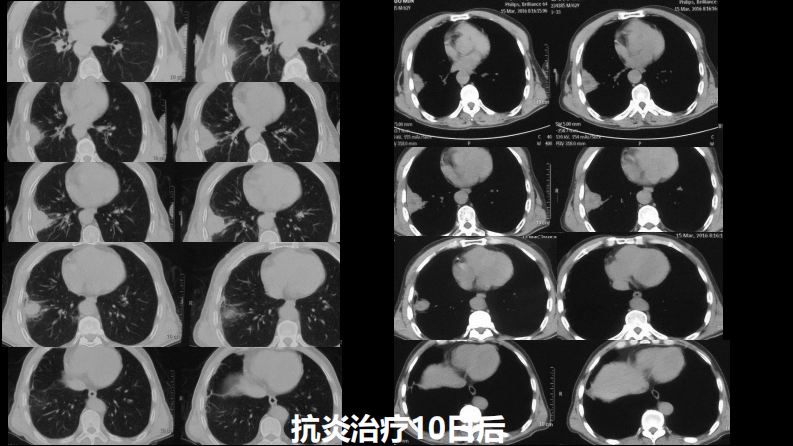

肺部肿块有效的影像检查选择.pdf